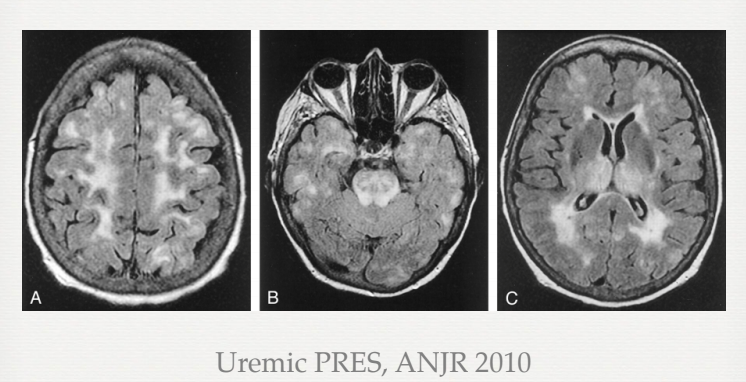

Estudo de imagem para excluir isquemia ou hemorragias

- pode haver atrofia cerebral ou (especialmente em DM) aumento do sinal nas regiões corticais e subcorticais em regiões frontal, parietal e occipital ==> edema localizado

- PRES ou hipersinal bilateral em T2/FLAIR em gânglios da base

Achados

PRES

Referência : Uremic PRES, ANJR 2010